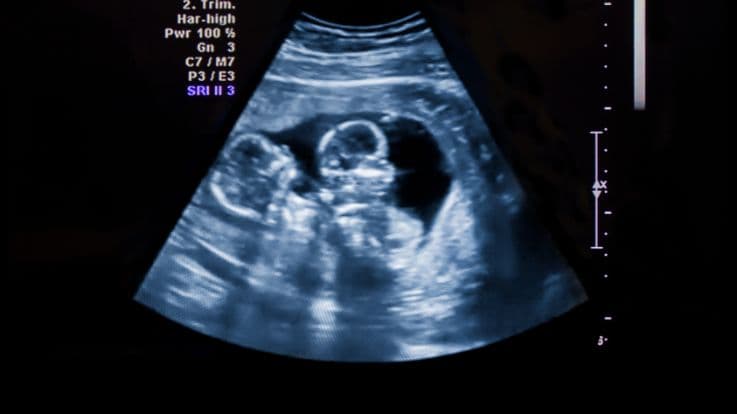

Can Ultrasonography Indicate Heteropaternal Superfecundation?

There are certain noteworthy changes that may be evident during ultrasonography, in the case of Heteropaternal Superfecundation. The earliest of these is that there are multiple gestational sacs in the mother’s uterus, each carrying 1 twin, who have distinct genetic makeup. The twins also have separate placentas.

The size, as well as the rate at which the fetuses grow may vary, based on their genetic makeup. This becomes more evident in the later stages of the pregnancy. They can show different movements & activity levels, rest in different positions, and respond in different ways.